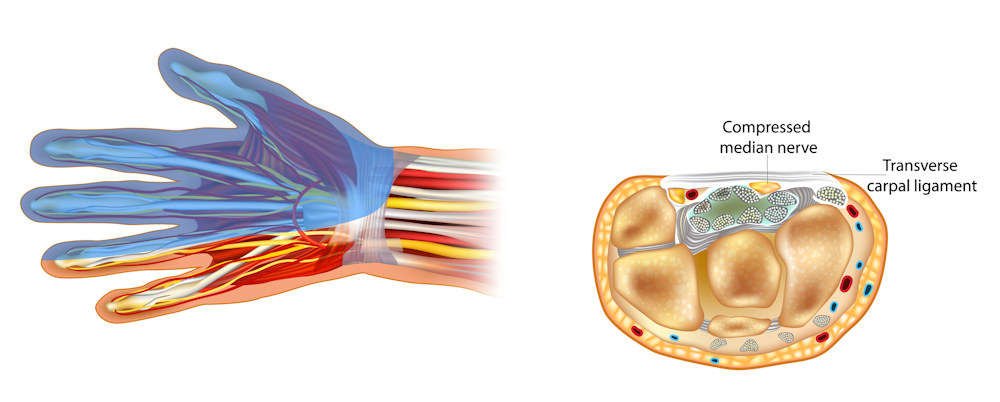

Carpal tunnel syndrome is numbness in your fingers from too much pressure on the median nerve at your wrist.

Nerves give sensation to your fingers and strength to the small muscles in your hand.

When the nerve is 'squeezed' or compressed, a patient will feel tingling or numbness in the hand that can travel up the arm.